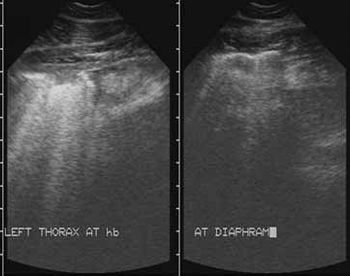

This case represents what clinical impression indicates is the most common form of pleuropneumonia seen in equine practice.